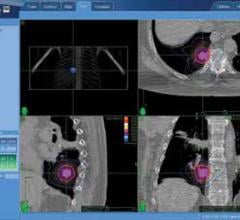

Augmenix Inc. announced U.S. Food and Drug Administration (FDA) clearance of the SpaceOAR System, cleared as a spacer to protect the rectum in men undergoing prostate cancer (PCa) radiotherapy. Despite many advancements in PCa radiotherapy, the close prostate-rectum proximity makes it challenging to deliver adequate radiation to the prostate without injuring the rectum (defined as the Organ At Risk - OAR). The SpaceOAR System is intended to temporarily position the anterior rectal wall away from the prostate during radiotherapy for PCa.